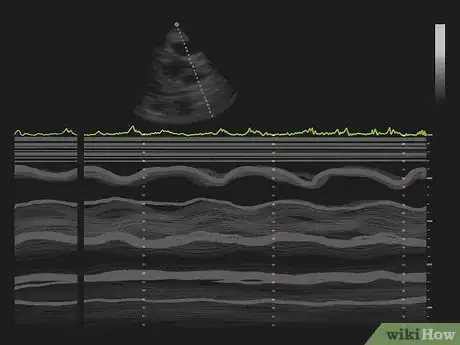

Watch the monitor to determine what techniques the doctor uses. There are several different techniques the doctor may use. They enable the doctor to make different measurements.[9]

• M-Mode. This technique generates a outlines showing the heart's size, the chambers, and the thickness of the walls of the heart.